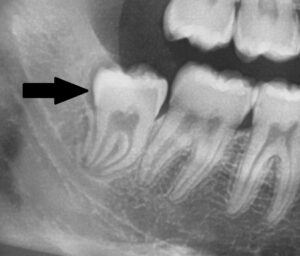

Weisheitszahn kann Zähne verschieben – Auf dem ersten Röntgenbild ist ein Weisheitszahn (schwarzer Pfeil) abgebildet, dessen Wurzelwachstum noch nicht abgeschlossen ist. Lediglich die Zahnkrone dieses Zahnes ist ausgebildet. Auf der nächsten Abbildung ist die Zahnachse des gleichen Weisheitszahnes (blaue Linie) und des Nachbarzahnes (grüne Linie) dargestellt. Im Rahmen des Wurzelwachstums kann der Weisheitszahn die davorliegenden Zähne verschieben. Besteht die Gefahr, dass der kieferorthopädische Behandlungserfolg in Gefahr ist, dann sollten solche Weisheitszähne entfernt werden.